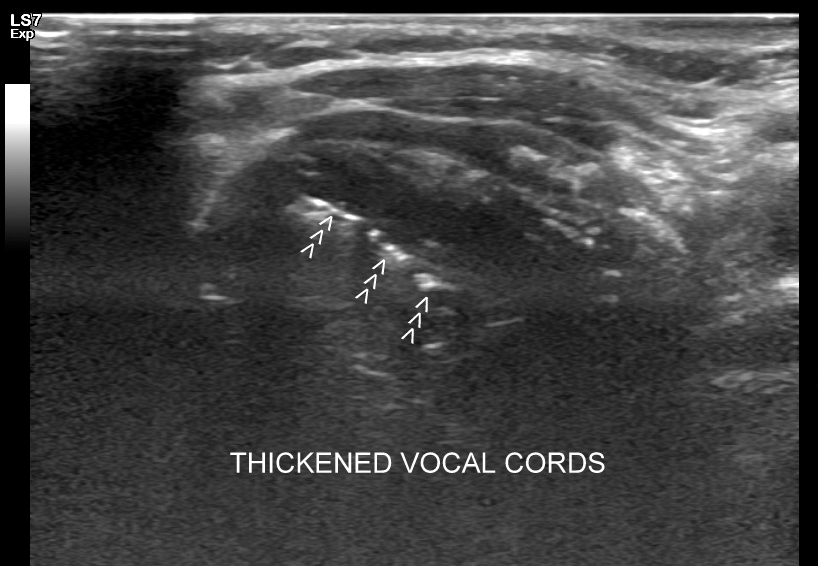

15. Wybrane patologie krtani i dróg oddechowych.